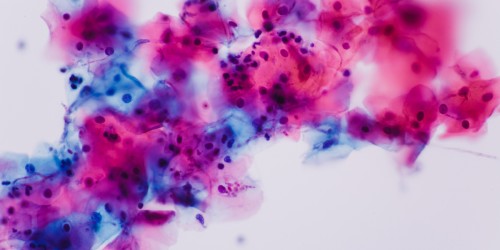

You could get bacterial infection even if you were 15. The bacteria is from the intestinal tract probably spread from anal area. It could come into contact with vaginal area by improper wiping after peeing or after bowel movements.